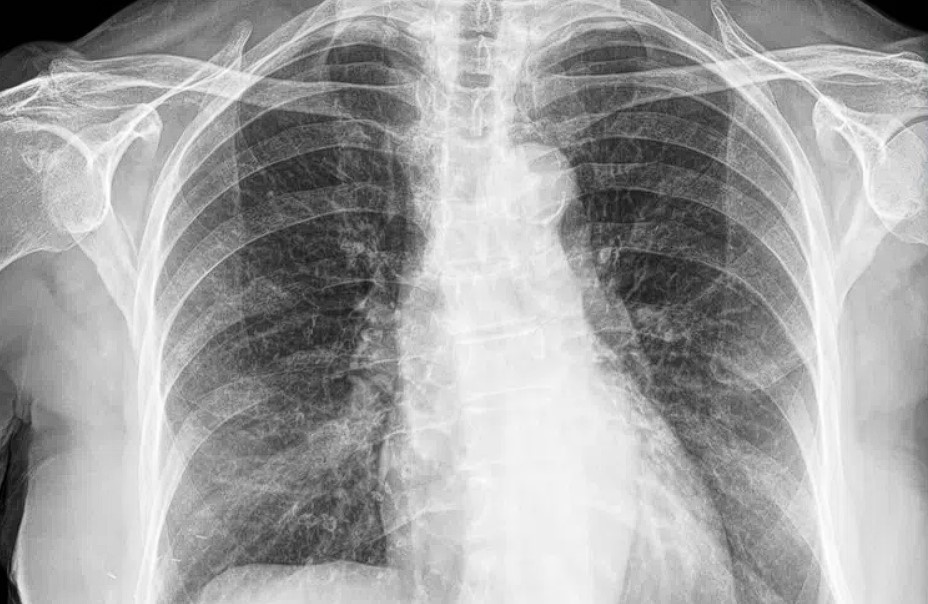

Radyolüsent alanlar ışığı geçirdikleri için koyu renkte görünürler. Bu noktada kemik dokuları ile ilgili bir örnek vererek konuyu açıklığa kavuşturmak istiyorum. Kemik dokusu radyolüsent değildir ve röntgende görüntülenirken ışığı geçirmez ve emer. Dolayısıyla daha parlak görünürler. Radyolüsent olmayan yapılar radyoopak olarak isimlendirilir.

Şekilde bir röntgen filmini görüyorsunuz. Bu filmde kemikler radyolüsnt değil radyoopak görünümdedirler.